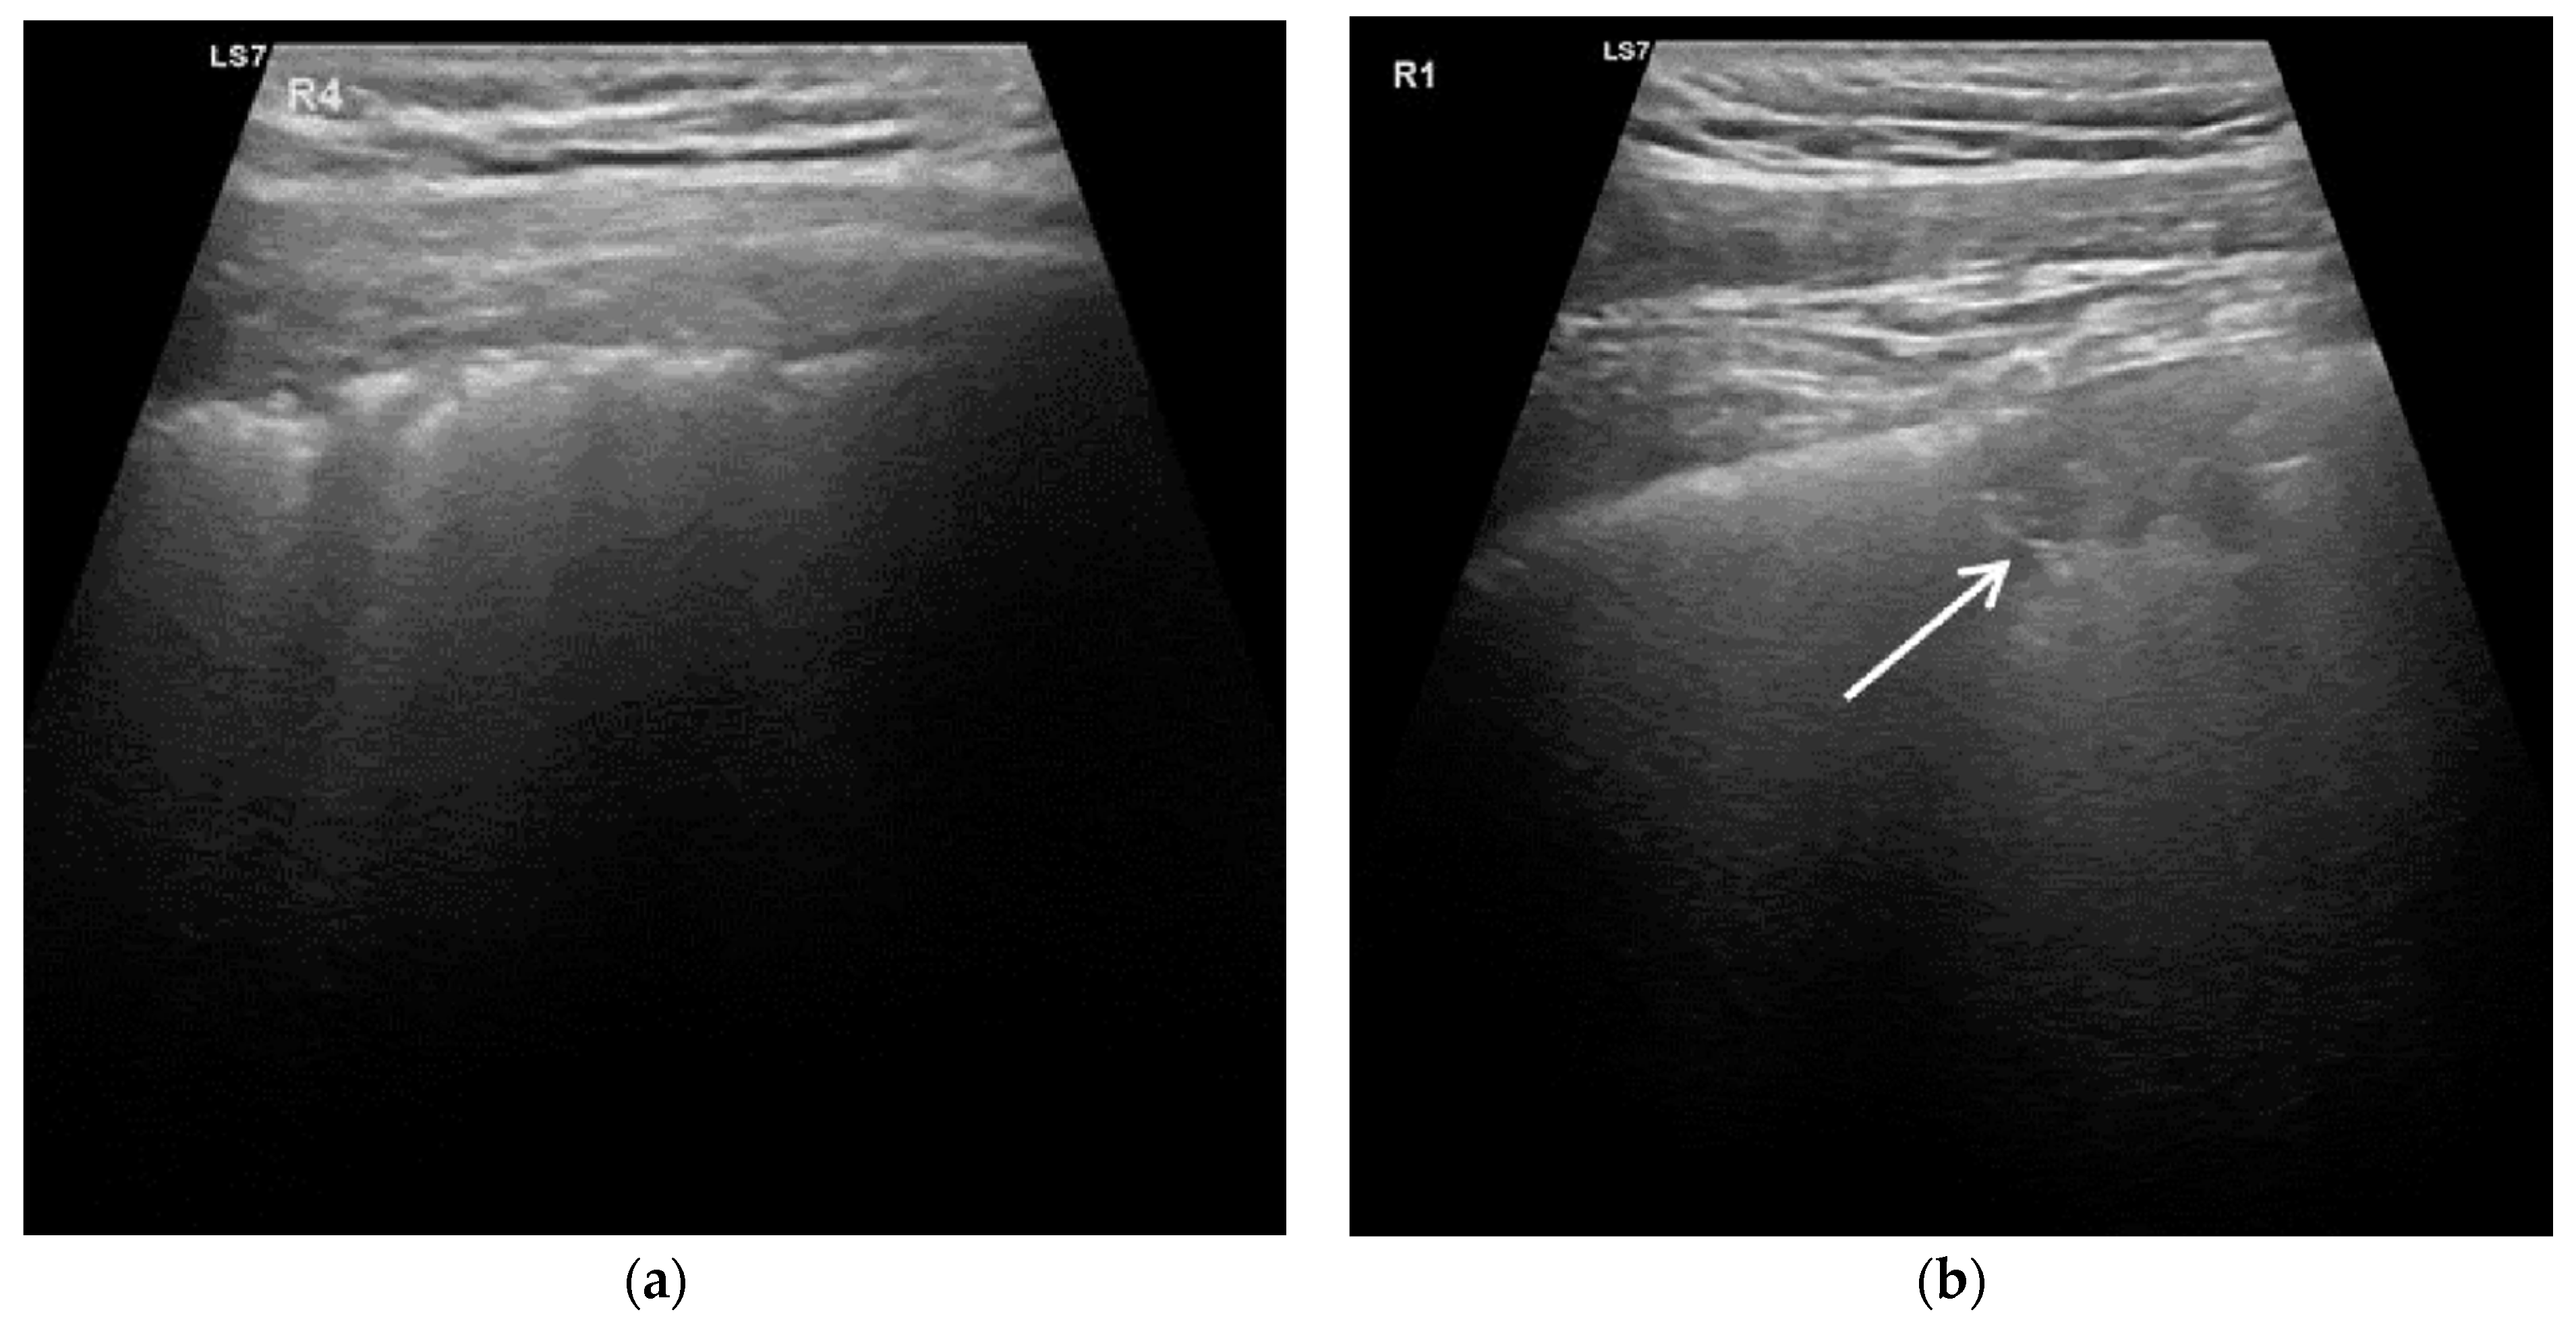

- Score 0: inconspicuous continuous pleural line, possible A-lines, visible or invisible B-lines in a number ≤ 3 per field of view;

- Score 1: B-lines (number > 3) or white lung syndrome (WLS), irregular pleural line or when pleura appears as thickened on sonography (thickened pleural);

- Score 2: pleural fragmentation with possible sub-pleural small consolidations (<1 cm);

- Score 3: larger consolidation >1 cm with or without aero-bronchogram.